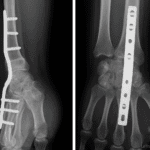

Interventions chirurgicales de la Tendinite du Poignet

Dans les cas graves où les tendons sont gravement endommagés, une intervention chirurgicale peut être nécessaire. Cependant, la chirurgie est généralement envisagée en dernier recours après l’échec des traitements conservateurs.